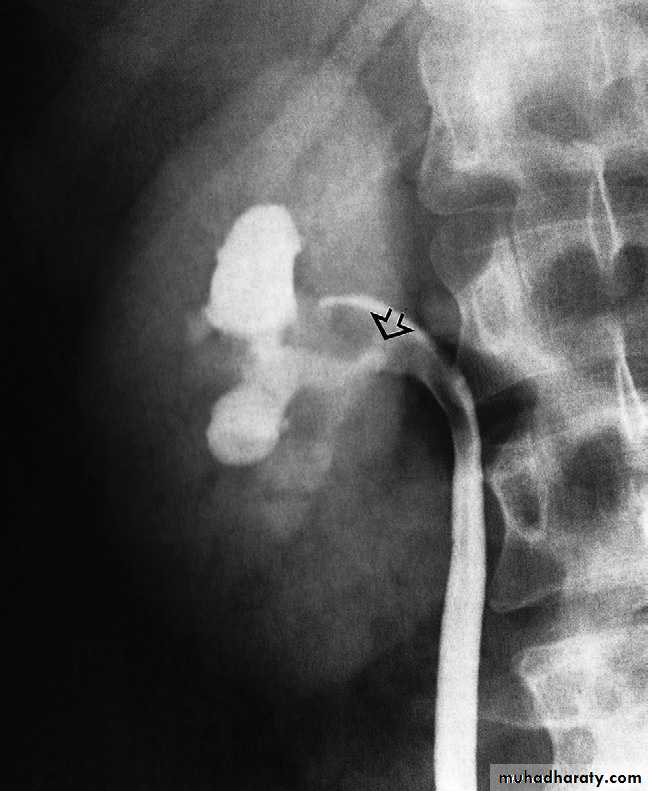

-Congenital intrinsic pelviureteric junction obstruction(PUJ obstruction ):The diagnosis depends on identifying dilatation of the renal pelvis and calices, with an abrupt change in calibre at the PUJ with normal ureter .

Extrinsic causes of obstruction